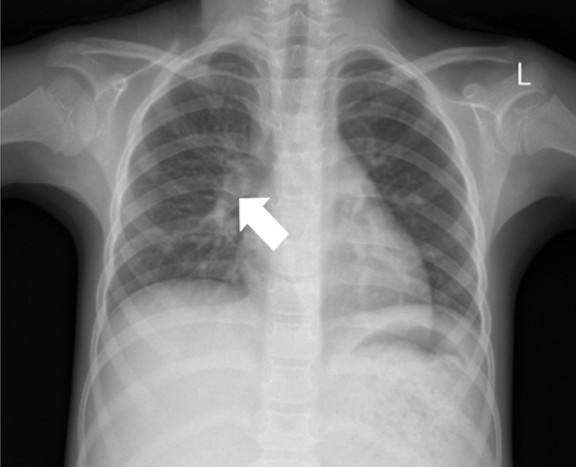

The abdominal X-ray showed distension and a sentinel loop in the left upper quadrant (Figure 1A), while the ultrasound revealed ascites (Figure 1B). The MTB/RIF Ultra (Cepheid, Sunnyvale, California, USA) test on sputum was negative, but a positive tuberculin test showed a 20 mm induration. A chest X-ray revealed hilar lymphadenopathy (Figure 2), giving a TB score of eight. Subsequently, to assess for extrapulmonary TB (EPTB), an ascitic fluid sample was obtained via laparoscopic examination. During the procedure, multiple whitish tubercles were observed (Figure 3A). Although the MTB/RIF Ultra test of the fluid was negative, the adenosine deaminase (ADA) level was elevated at 58 U/L, and histopathology confirmed abdominal TB with epithelioid granulomas and Langhans giant cells (Figure 3B). The HIV test was nonreactive.